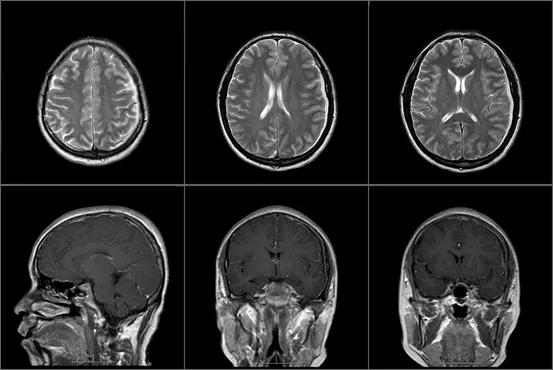

“今天不去医院我也得拉你去了。”我逼着梁请了一天的年假,到医院做了检查,但核磁看不出异样,在门诊开了些药物后就让我们回去了。

急诊做了颅脑核磁平扫增强,医生告诉我们,梁的颅脑影像多发强化,左侧额颞顶枕部硬膜下积脓,考虑是感染性病变引起的脑膜脑炎。